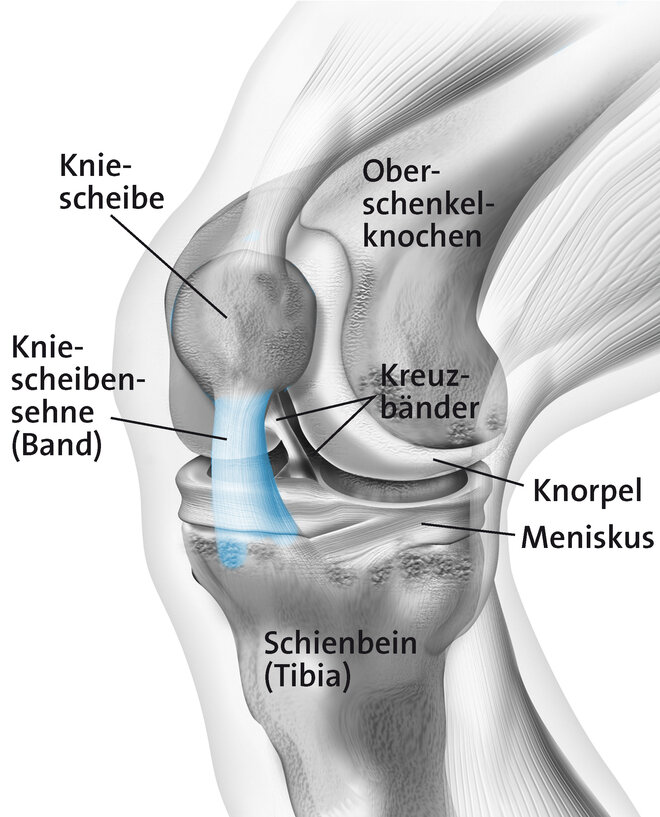

Durch Überbelastung der Kniescheibensehne (Patellarsehne) kommt es an ihrem Ursprung am Unterrand der Kniescheibe zu kleinsten Verletzungen und Auffaserungen der Sehne. In der Nähe bildet sich neues Bindegewebe, Nerven und Blutgefäße sprießen ein. Ärzte sprechen auch von degenerativen Veränderungen. Der allgemeine Fachbegriff ist Tendinopathie (= Sehnenleiden). Zu einer Überlastung der Patellarsehne kommt es vor allem durch sportliche Aktivität, insbesondere bei sogenannten Schnellkraft-Sportarten mit raschen Richtungswechseln, abruptem Abbremsen ("stop and go") und starker Belastung beim Springen und Landen wie beispielsweise Volleyball oder Handball. Daher auch der Begriff Springerknie (englisch: jumpers knee). Betroffen können ein oder beide Knie sein. Meist ist die Sehne am unteren Pol der Kniescheibe betroffen (Insertionstendinose).

Tendinopathien, also Schmerzen an den Sehnen können an verschiedenen Stellen auftreten. Beim Jumpers-Knee handelt es sich um eine Entzündung am Ansatz der Sehne (Insertionstendinose) am unteren Pol der Kniescheibe. Diese tritt vor allem beim sportlichen Erwachsenen auf. Treten die Beschwerden bereits beim Jugendlichen auf handelt es sich meist um einen Morbus Sinding-Larson-Johansen. Auch hierbei kommt es durch Überbelastung zu einer Entzündung am Ursprung der Patellarsehne, bei welcher aber ein Teil der Kniescheibe mitabsterben kann (Osteonekrose).

Hintergrundinformation - Das Kniegelenk

Wichtigste Eckpfeiler der konservativen Therapie sind eine Sportpause oder zumindest die Umstellung auf schonendere Bewegungsabläufe, eine Physiotherapie (Übungsbehandlung, Massagen, Elektrotherapie und Kühlung) ergänzt durch eine spezielle Trainingstherapie (exzentrisches Krafttraining, siehe separater Kasten). Gegebenenfalls können auch schmerz- und entzündungshemmenden Medikamente zum Einsatz kommen.

Neben der "klassischen" Physiotherapie kommen auch Massagen, Kälteanwendungen und Elektrotherapie zum Einsatz. Ergänzend können spezielle Tapes oder Bandagen helfen, die Sehne ruhigzustellen und die Kraftübertragung zu entlasten.